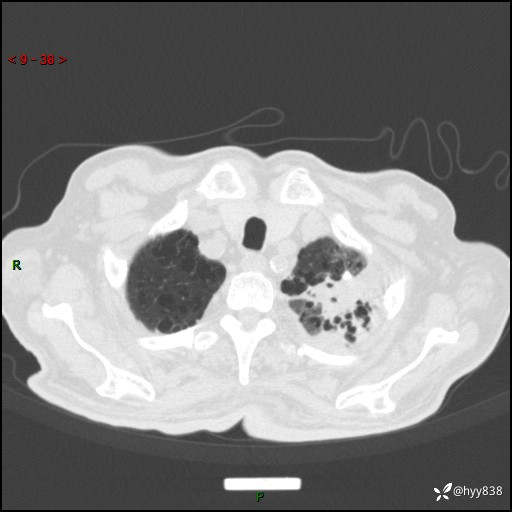

老年男性,间断咳嗽咳痰20余年,加重伴发热1天。呼吸科疑难病例讨论---结果公布

主诉:间断咳嗽咳痰20余年,加重伴发热1天

简要病史:家属代诉患者于20余年前无明显诱因出现咳嗽咳痰,痰为白色泡沫状,未行特殊治疗,不伴胸痛、胸闷、气喘、咳血等不适,1天前上午患者无明显出现发热,查体温39℃,伴咳嗽,咳痰无力,自行予以物理降温对症治疗,今晨2点左右再次出现发热,体温达40℃,自行服用复方氨酚烷胺对症治疗,凌晨3点左右复测体温38.2℃,现患者为求进一步诊治于今日就诊于我院门诊,行胸部CT提示双肺感染,遂以“肺部感染”收入我科。 患者本次起病来精神、食欲、睡眠欠佳,体力下降,体重无明显变化。

辅助检查:CT

胸部CT平扫